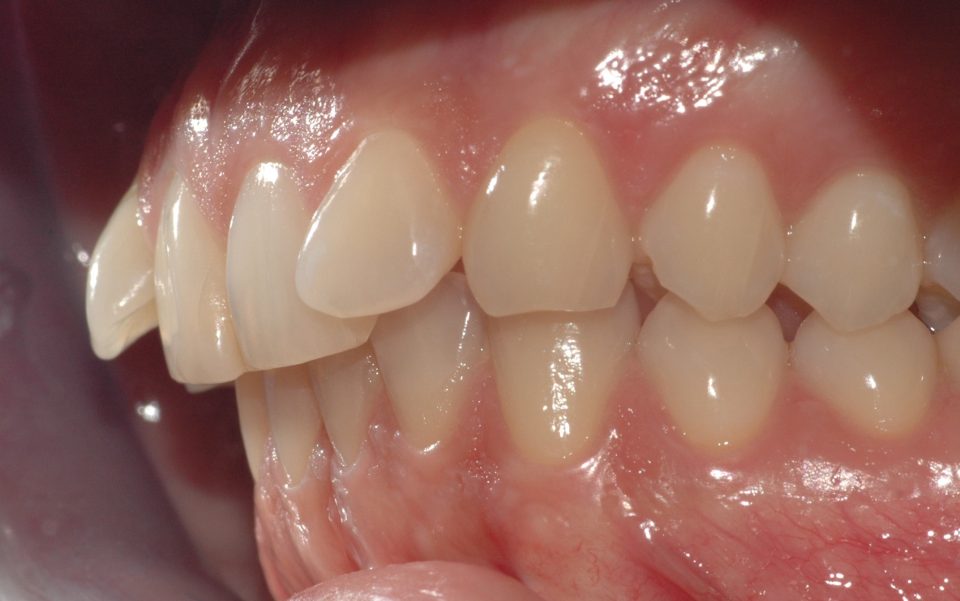

Caso clinico

La paziente si presenta a causa del malposizionamento del canino superiore di sinistra, ruotato lungo il suo asse di quasi 90 gradi. In seguito ad un trattamento con allineatori trasparenti di circa 7 mesi, il dente è stato portato in posizione assolutamente idonea.